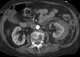

Idiopathic renal hypercalciuria

Kidney stone disease, also known as nephrolithiasis or urolithiasis, is when a solid piece of material (kidney stone) develops in the urinary tract. Kidney stones typically form in the kidney and leave the body in the urine stream. [Source: Wikipedia ]